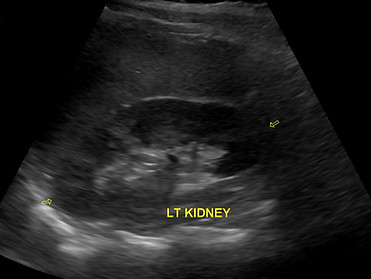

Kidney Ultrasound

Kidney or Renal Ultrasound specifically looks at the anatomy, size and details of the kidney